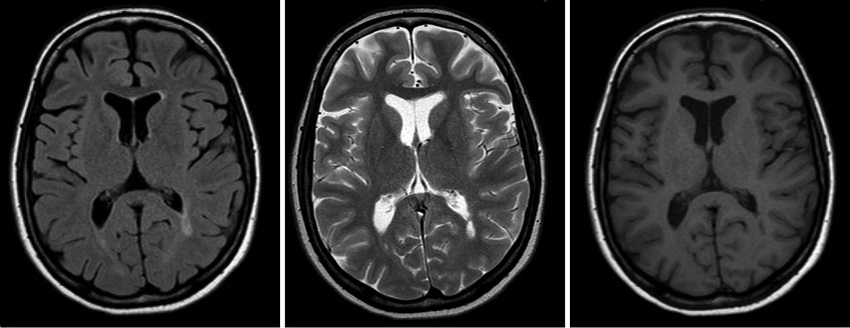

КТ головного мозга - современный рентгенологический метод диагностики, позволяющий исследовать структуры и функциональное состояние головного мозга, диагностировать различные заболевания на ранних стадиях развития.

КТ с высокой четкостью визуализирует состояние костей, мозговой оболочки, структурных особенностей мозга, околоносовых синусов.